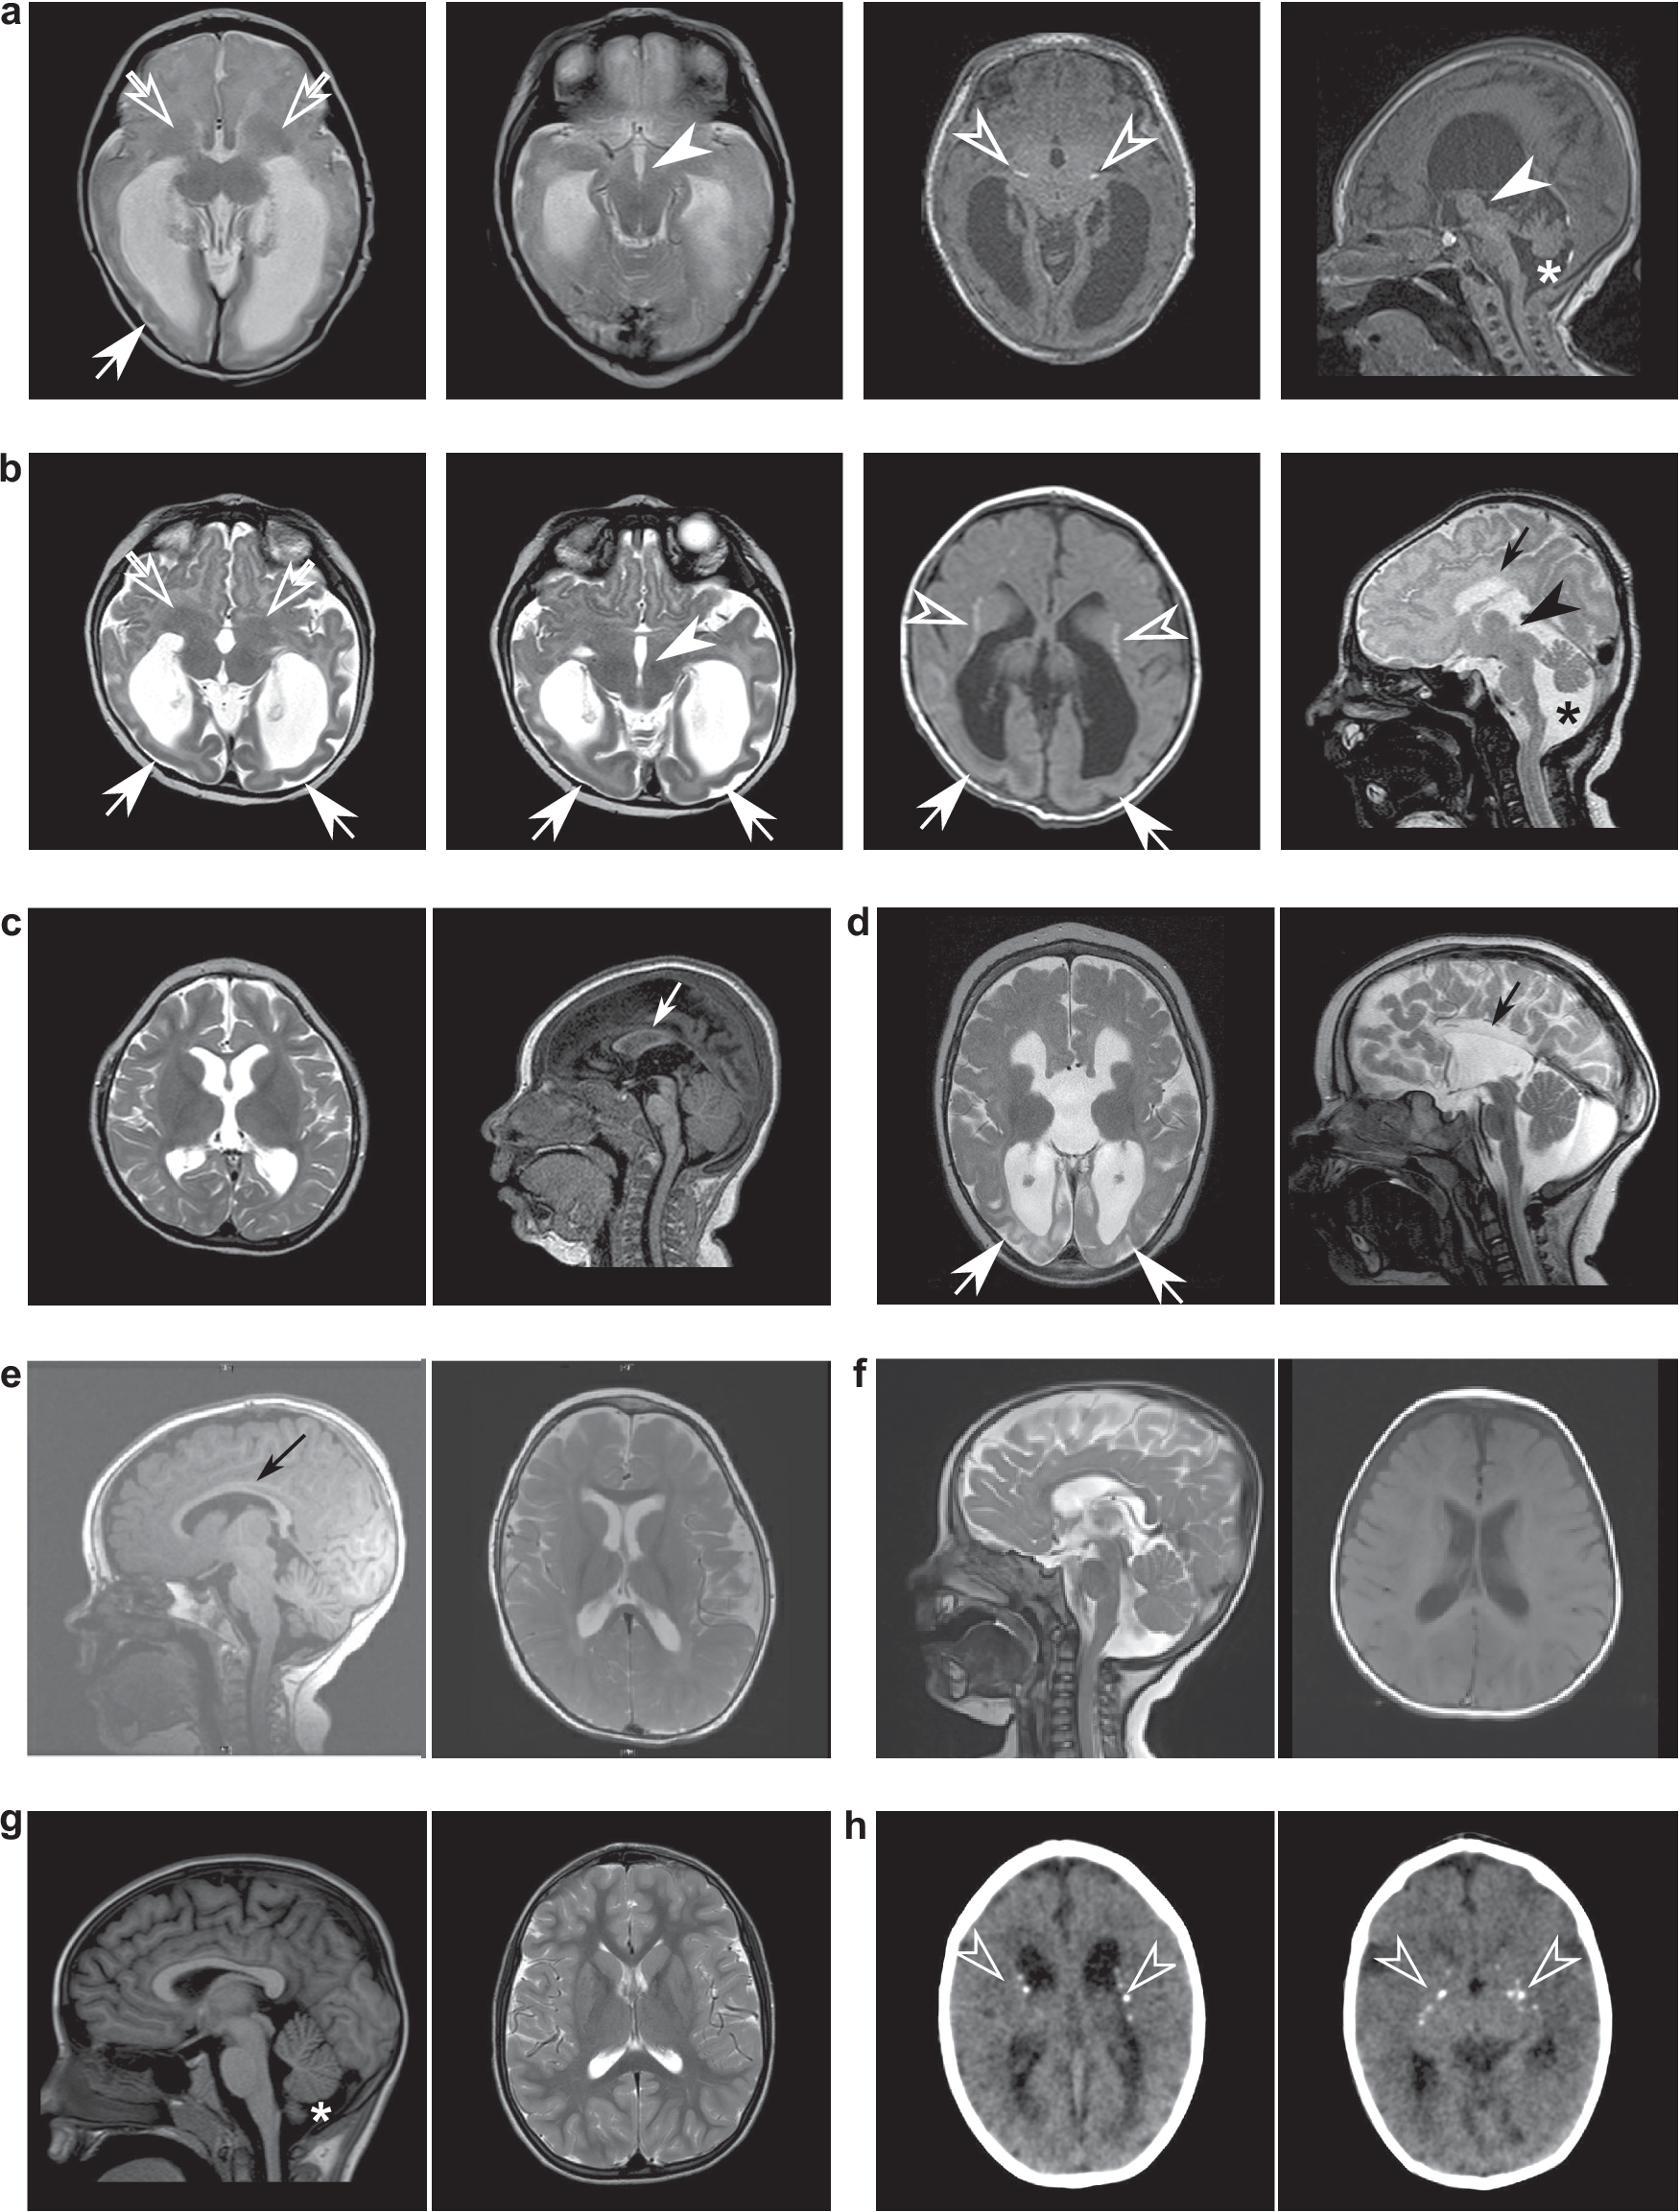

Fig. 2: Neuroanatomical heterogeneity in individuals with biallelic DENND5A variants.

Representative MRI slices from unrelated individuals with (a) homozygous p.Q1271R*67 variants (participant 5); (b) homozygous p.S728Qfs*34 variants (participant 14); (c) compound heterozygous p.K485E/p.R710H variants (participant 2); (d) compound heterozygous c.2283+1 G > T/p.K1007Efs*10 variants (participant 18); (e) compound heterozygous individual with variants c.950-20_950-17delTTTT/p.R1078Q (participant 9); (f) compound heterozygous individual with variants p.R1032T/p.T1039N (participant 30); and (g) compound heterozygous individual with variants p.K485E/p.R1159W (participant 8). h CT images from a homozygous individual with the variant p.V1202Afs*52 (participant 25). Arrows = posterior gradient of pachygyria/lissencephaly; open arrows = basal ganglia dysmorphism; arrowheads = diencephalic/mesencephalic junction dysplasia; open arrowheads = calcifications; small arrows = corpus callosum dysgenesis/agenesis; asterisks = cerebellar hypoplasia.